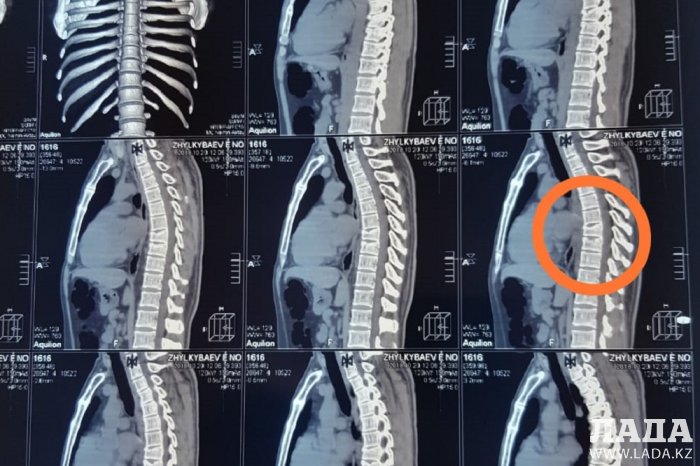

- Трасса не освещается. Верблюда увидел уже поздно. Решил уйти от столкновения с ним и вылетел на обочину. После того, как пришел в себя, вылез из машины. Две машины проехали мимо, хотя видели меня и мой автомобиль. Помогли ребята, которые ехали за мной. Меня отвезли в больницу поселка Шетпе. Там осмотрели и отправили в в областную больницу Актау. Врачи сказали, что ничего серьезного, и отправили домой. Уже на следующий день после обследования в частной клинике выявили травму трех позвонков, – рассказал Есен Джилкибаев.